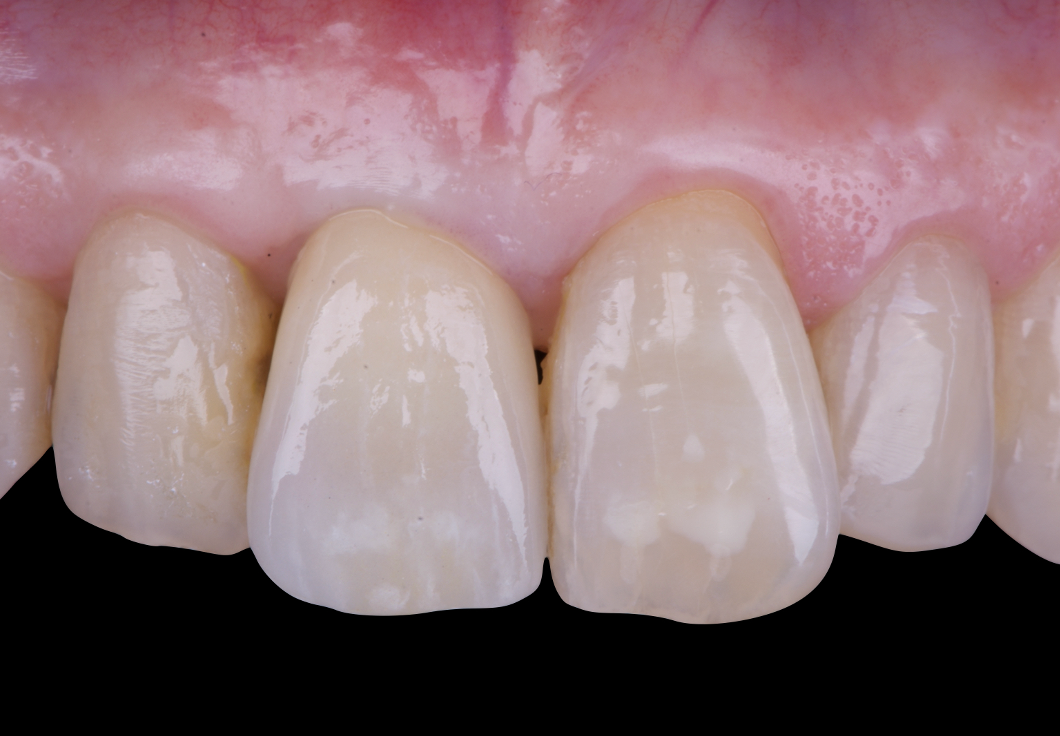

After an appropriate healing period, the definitive prosthesis was planned and delivered. A screw-retained zirconia crown was fabricated to ensure long-term durability, optimal esthetics, and retrievability. Zirconia was selected for its mechanical strength and excellent esthetic properties, blending seamlessly with the adjacent natural dentition in both form and color.

The final crown was designed to maintain the gingival architecture that had been shaped by the provisional. Special attention was paid to the emergence profile, contact points, and translucency to achieve harmony with the patient’s smile. The definitive restoration provided functional stability and esthetic integration, fulfilling the patient’s expectations for a fixed and natural solution.